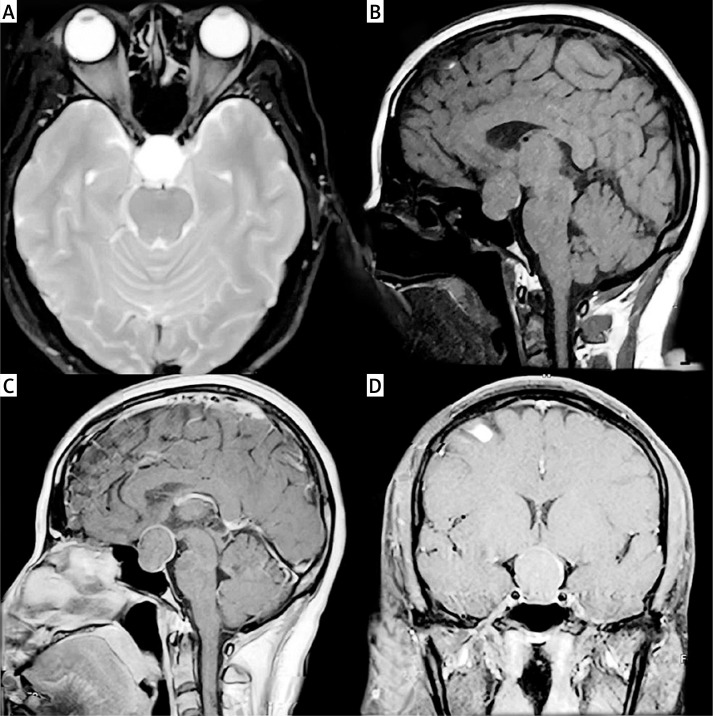

Effectiveness of endoscopic transnasal pituitary surgery versus antibiotic therapy in the management of pituitary abscess: a report of two cases.